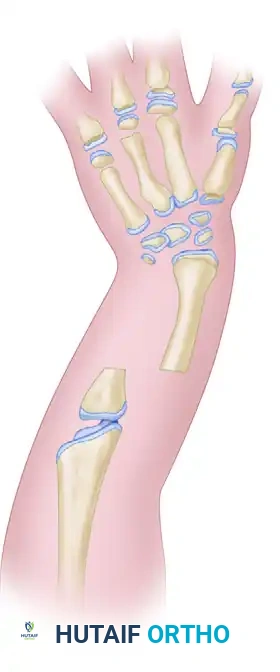

Image

Figure A: Resection of the distal ulnar anlage and the proximal radius (shaded areas).

Figure B: Alignment of the distal radius and proximal ulna to create a single osseous strut.

• Fix the construct rigidly. Pass a stout Kirschner wire (or Steinmann pin) antegrade through the olecranon, across the osteotomy site, and distally into the radial segment and carpus to ensure absolute stability.

Figure C: Kirschner wire extending into the carpals, used to stabilize the newly created radioulnar segment.

Composite Diagram: Creation of a one-bone forearm demonstrating resection, alignment, and K-wire fixation.